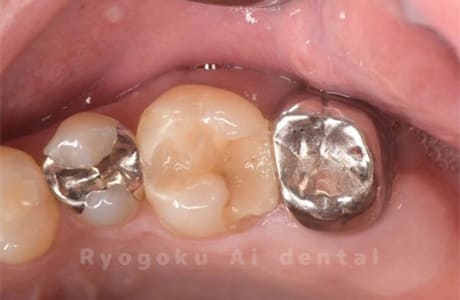

Case35

-

- 原因

- 重度カリエス

- 治療内容

- クラウンレングスニング、ジルコニアクラウン

- 治療費用

- 429,000円

他院で抜歯と言われた方です。手術をこない、保存を試みました。経過は良好です。

<リスク・副作用>

過度の咬合や衝撃で割れることがあります。術後は痛み、腫れ、痺れなどの副作用が生じる場合があります。